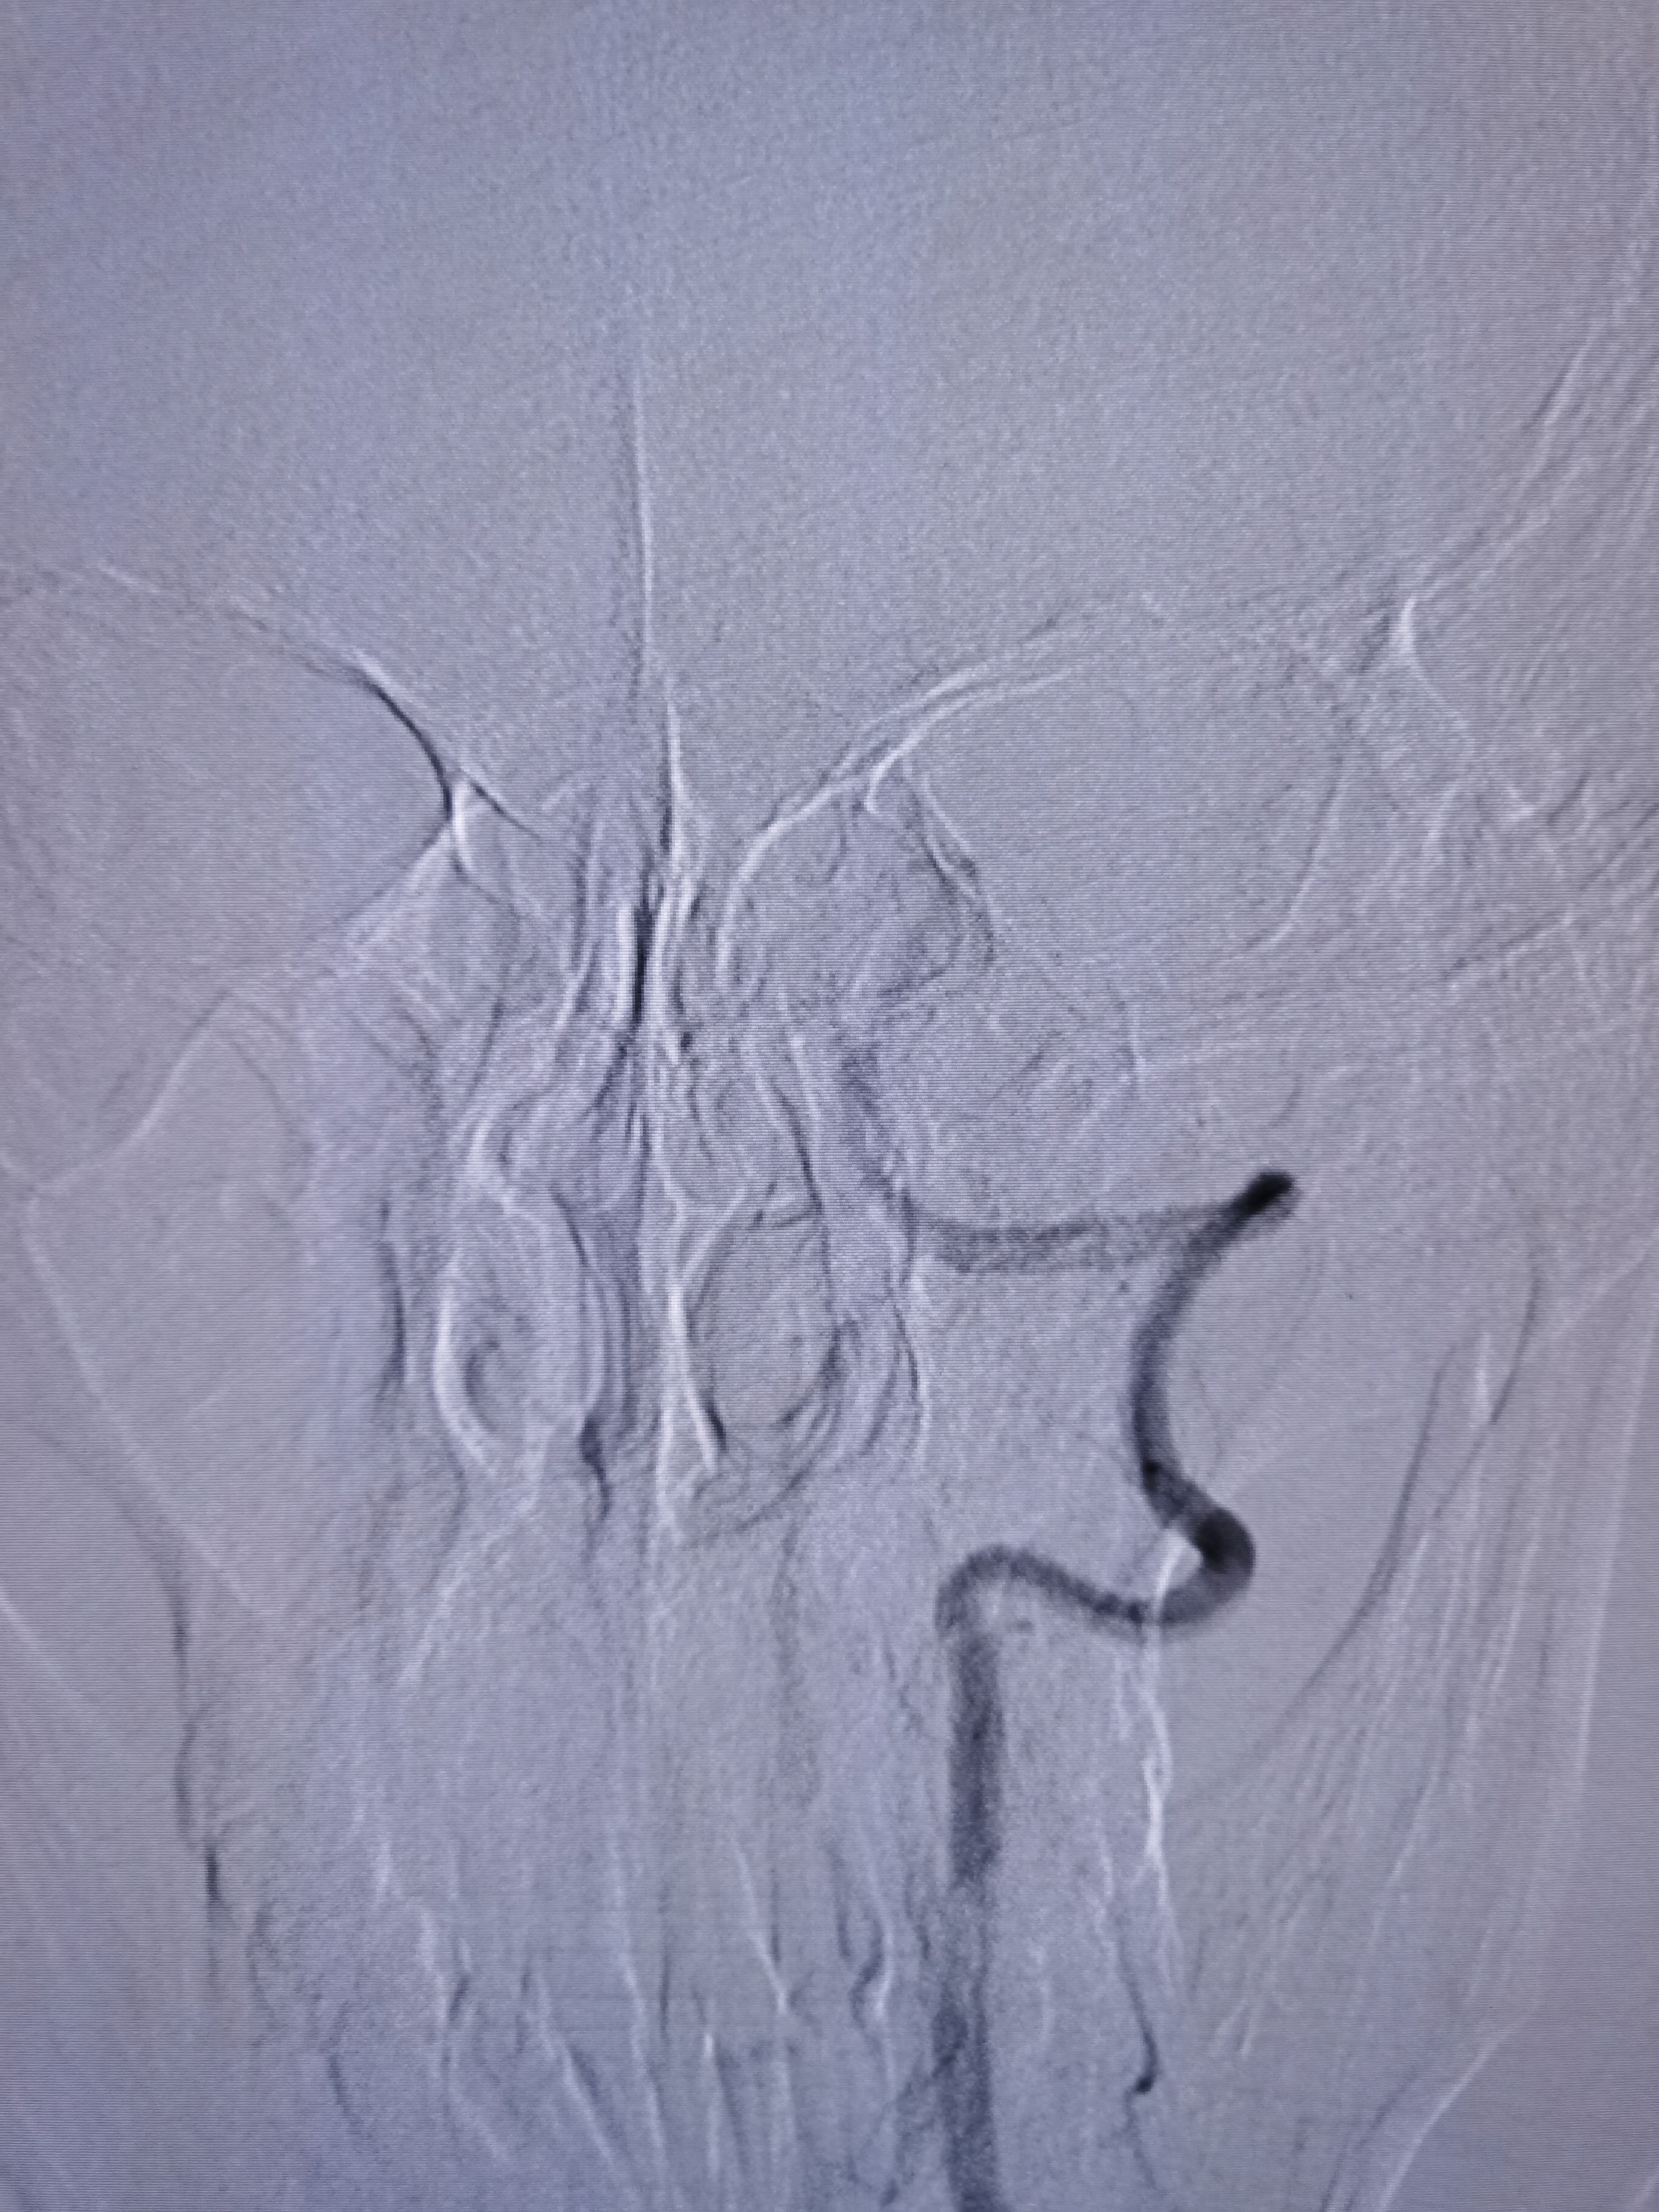

1、本例患者临床表现为头晕,恶心,呕吐后循环缺血症状,急诊CT除外出血后给予静脉溶栓治疗。经内科治疗后症状逐渐改善。但患者无卒中高危因素,需完善脑血管相关检查。

2、CTA证实左椎动脉起始部重度狭窄合并血栓,系责任血管,存在急性闭塞或残存血栓脱落至基底动脉风险,需积极处理。

3、手术过程中,先用小球囊扩张病变,观察血栓情况,及时应用支架全程覆盖血栓及病变部位,成形满意。